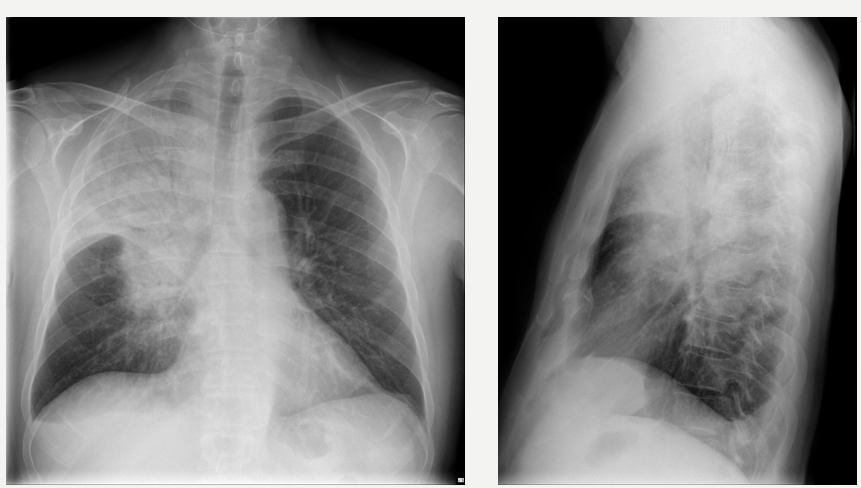

Findings generally cannot distinguish one type of infection from another

Multilobar infiltrates

S. pneumoniae or Legionella infection

Interstitial pneumonia

Increased interstitial markings and subpleural reticular opacities that increase from the apex to the bases of the lungs

Viral or mycoplasmal etiology

Cavitating pneumonia

S. aureus, fungal, or mycobacterial etiology